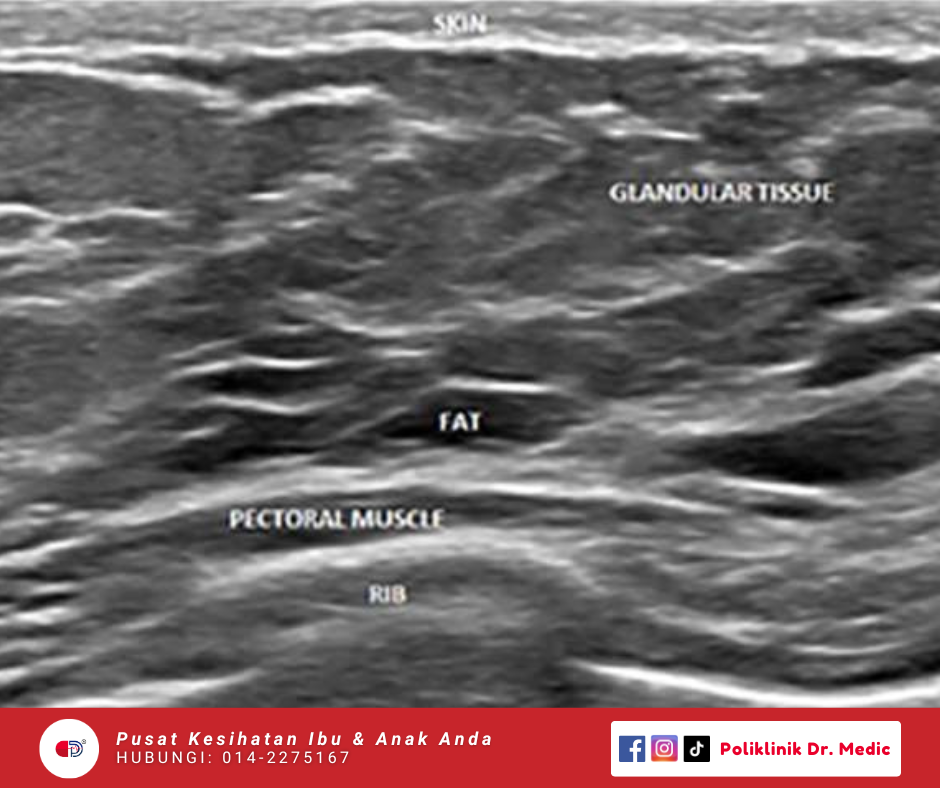

Breast Scan

Ultrasound Payudara untuk wanita. Pemeriksaan ini memang selamat dan tidak menyakitkan untuk kesan ketulan atau perubahan pada tisu payudara. Sesuai sebagai pemeriksaan awal atau susulan.

RM120